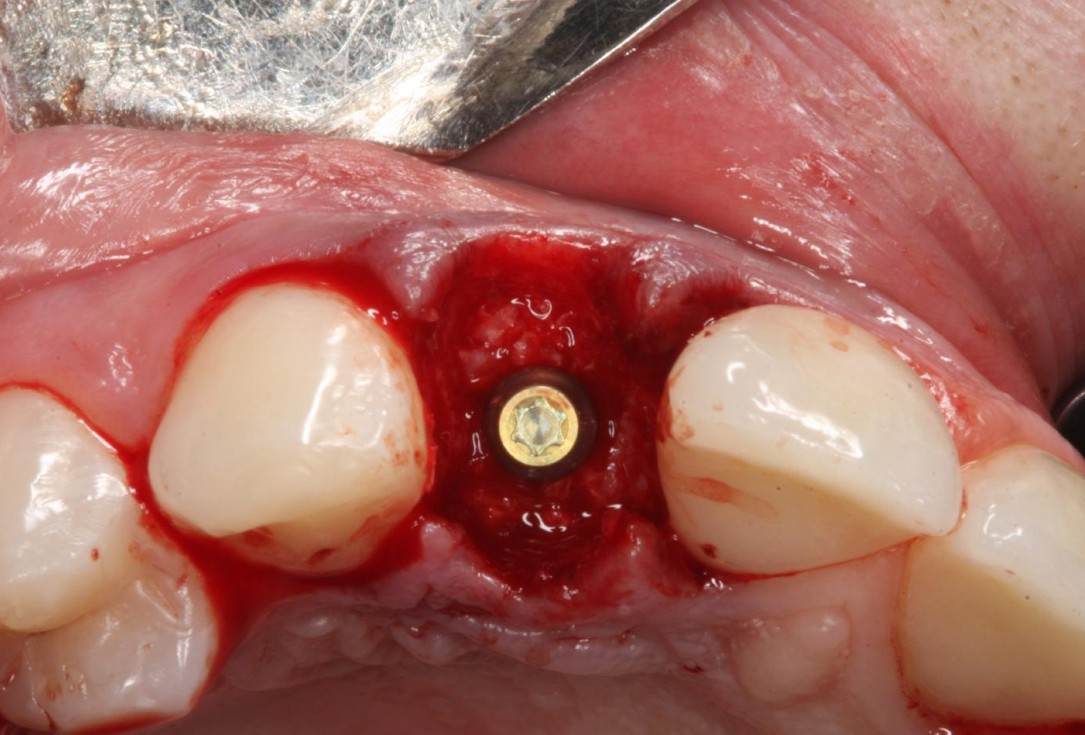

3/12 - Intact socketSoft tissue thickening at immediate implant placement and GBR with mucoderm® and maxgraft® - Dr. A. Puisys

Intact socket following atraumatic tooth extraction

Alveolar socket before soft and hard tissue augmentation